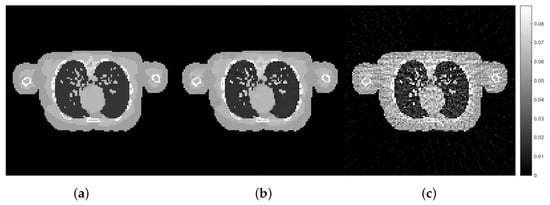

| Approaches | Relative Errors (%) | UQI | Computational Time |

|---|---|---|---|

| (h) | |||

| Hedge-based | 4.9349 | 0.9972 | 16.12 |

| Cross-validation | 5.2597 | 0.9970 | 47.15 |